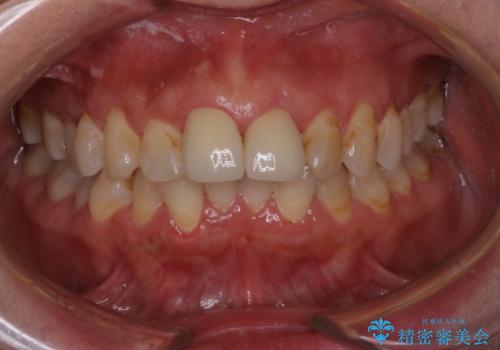

[ セラミック治療 ] 虫歯でつぎはぎになってしまった歯をきれいにしたい

担当医 大元洋佑

![[ セラミック治療 ] 虫歯でつぎはぎになってしまった歯をきれいにしたいの症例 治療前](https://seimitsushinbi.jp/wp/wp-content/uploads/2023/11/97b046ffd9b5b3b60d51f437c4943149-500x350.jpg?v=1700791880)

![[ セラミック治療 ] 虫歯でつぎはぎになってしまった歯をきれいにしたいの症例 治療後](https://seimitsushinbi.jp/wp/wp-content/uploads/2023/11/e5fb48a77a0a81d51a52e838569890a9-500x350.jpg?v=1700791903)